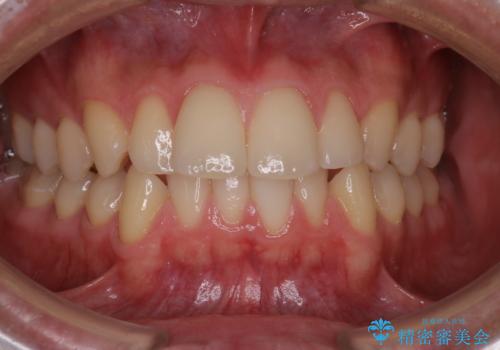

【クリア装置】八重歯とがたつきを綺麗に